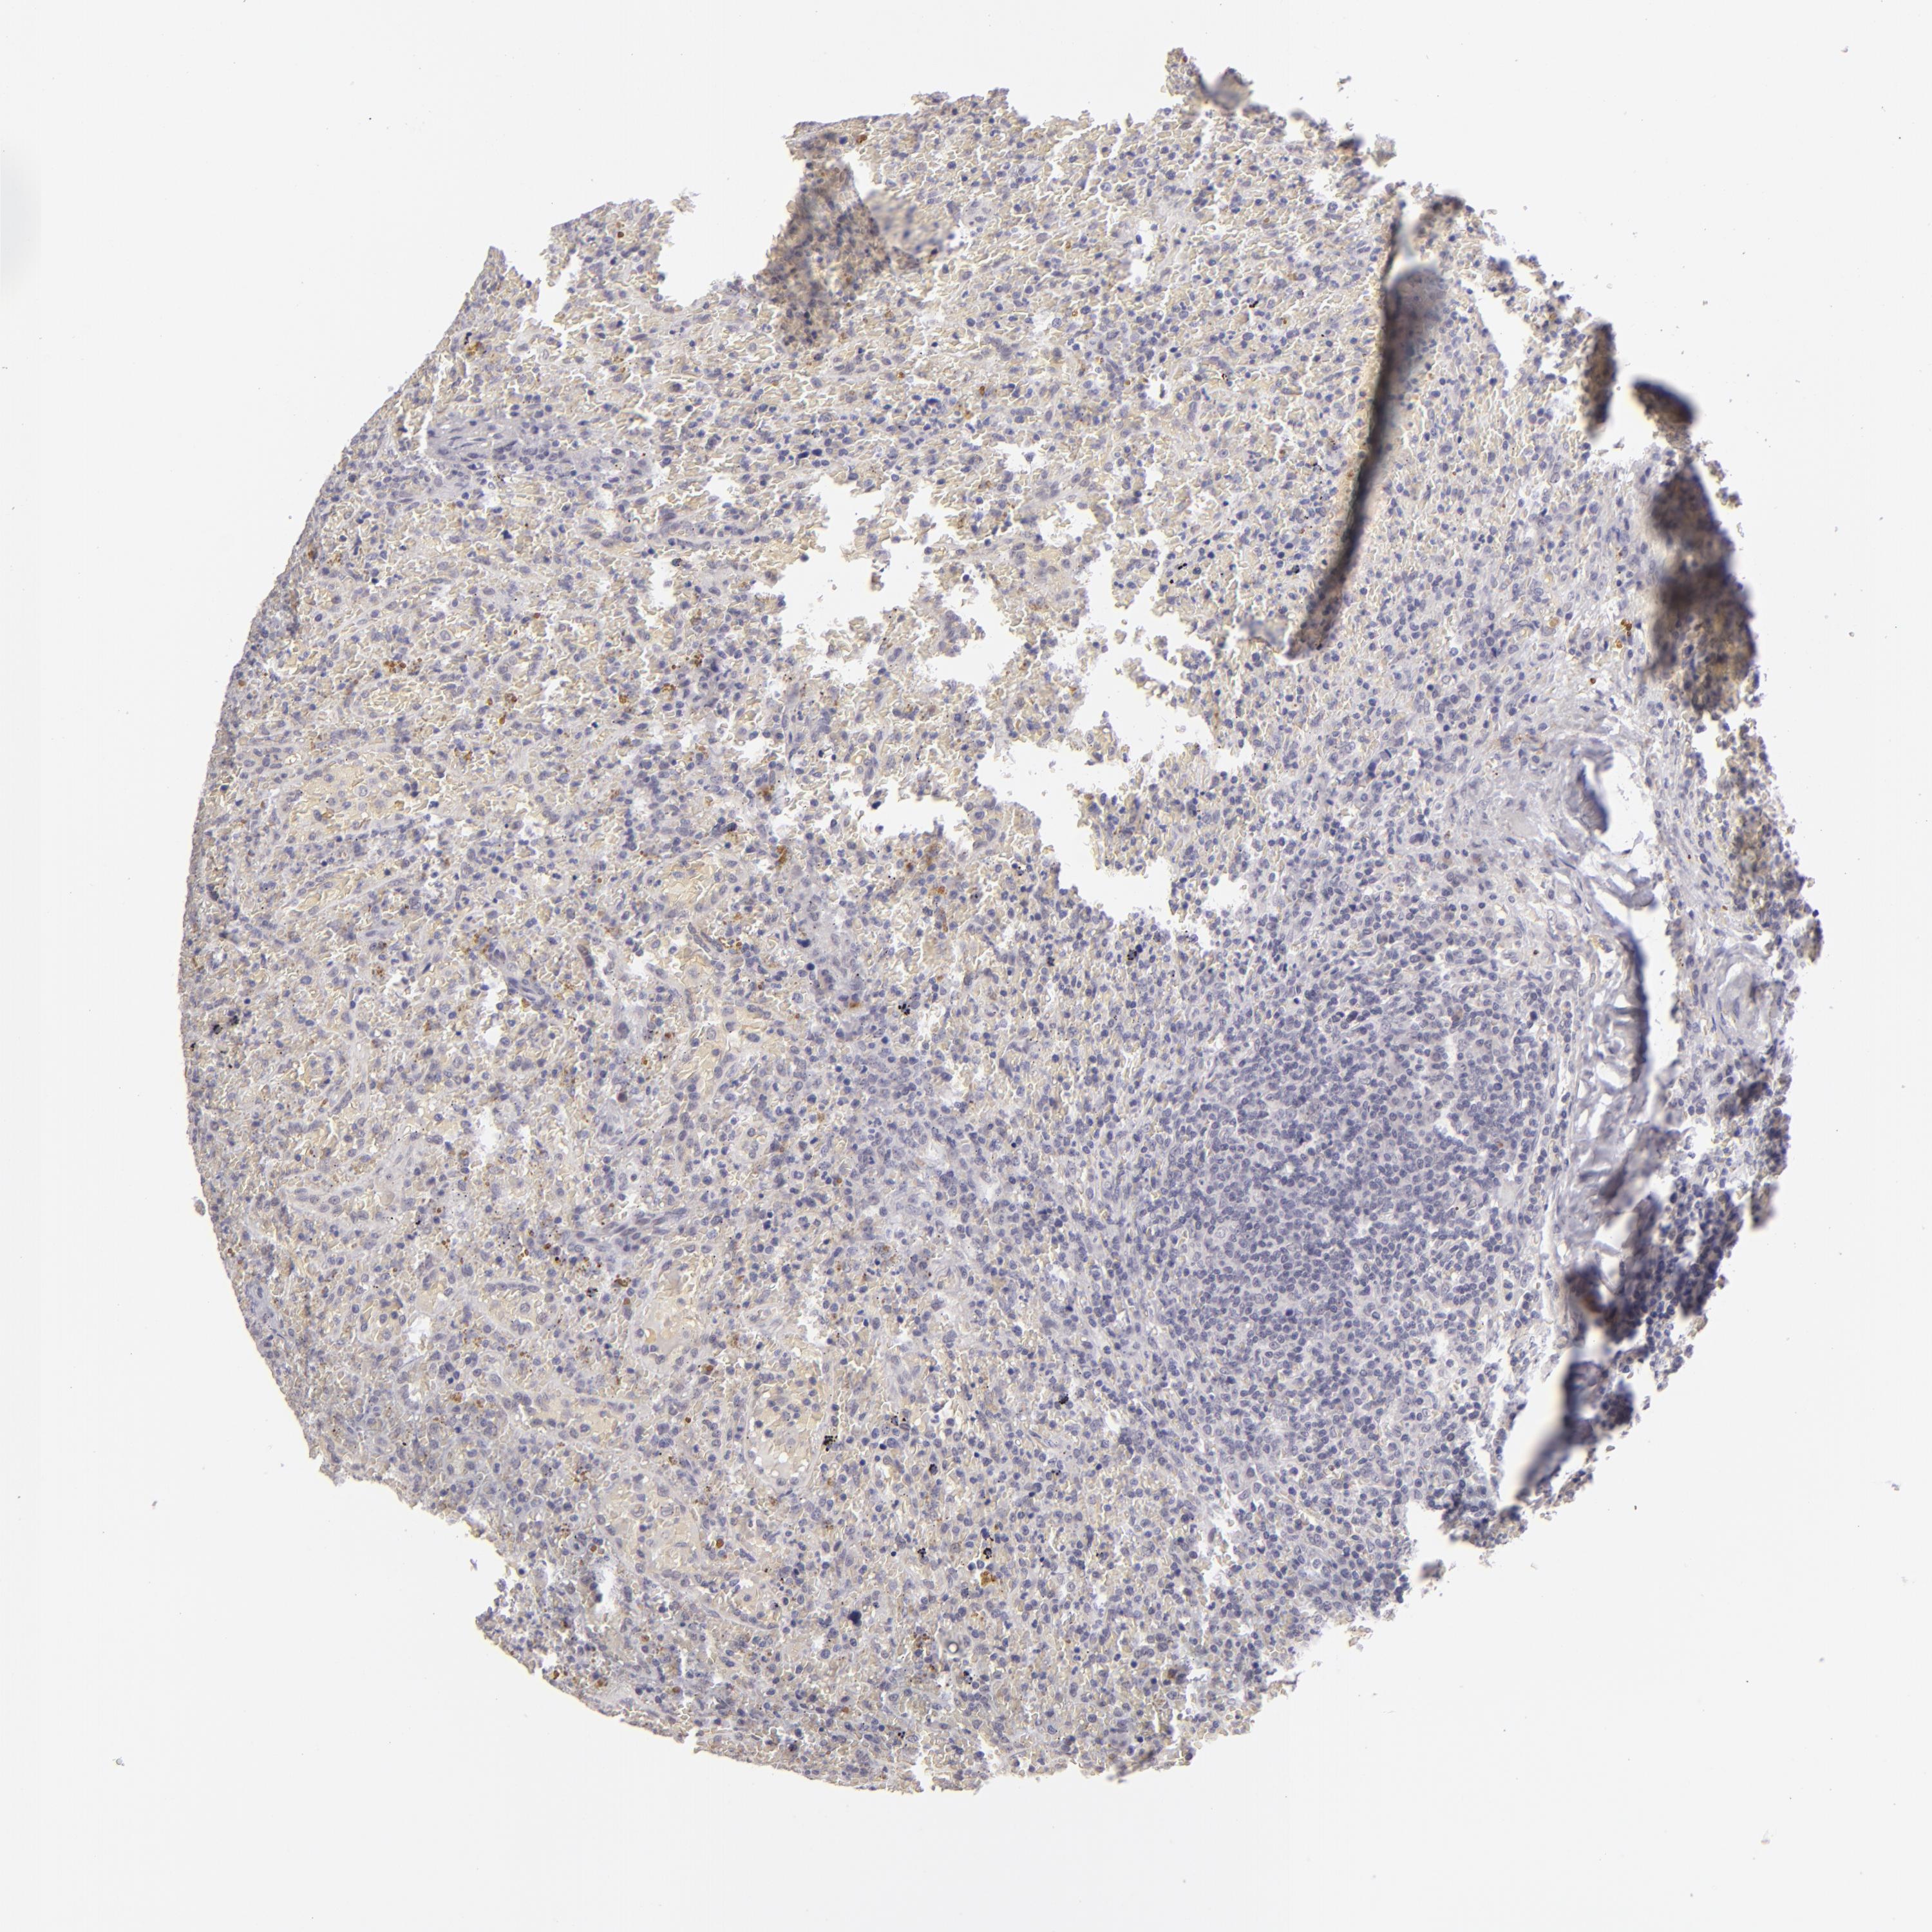

LYMPHOMA - Protein expressioni

A mouse-over function shows sample information and annotation data. Click on an image to view it in a full screen mode. Samples can be filtered based on level of antibody staining by selecting one or several of the following categories: high, medium, low and not detected. The assay and annotation is described here.

Each image is clickable and will lead to virtual microscopy that enables deeper exploration of all samples and also displays staining intensity scores, fraction scores and subcellular localization as well as patient and tissue information for each sample.

Antibody HPA001791

Staining

High

Medium

Low

Not detected

Intensity

Strong

Moderate

Weak

Negative

Quantity

>75%

75%-25%

<25%

None

Location

Nuclear

Cytoplasmic/membranous

Cytoplasmic/membranous,nuclear

Malignant lymphoma, non-Hodgkin's type, High grade

Hodgkin's disease, NOS

Malignant lymphoma, non-Hodgkin's type, Low grade